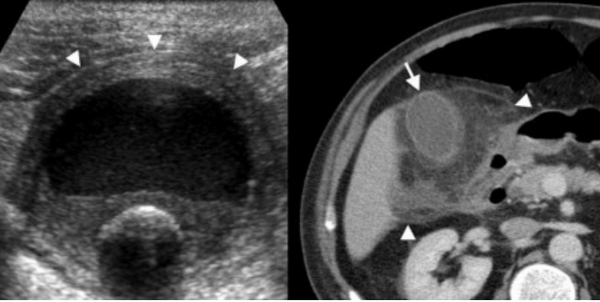

Ксантогранулематозный холецистит — это воспалительное заболевание, характеризующаяся тем, что в стенке желчного пузыря образуются ксантомы и гранулемы. При исследовании выявляют утолщение стенки желчного пузыря, уменьшение органа в размере, а также интрамуральные узелки, которые визуализируются, как гипоэхогенные включения на УЗИ и гиподенсные на компьютерной томограмме. Данные включения схожи с включениями при карциноме желчного пузыря.

УЗИ и КТ желчного пузыря. Ксантогранулематозный холецистит. Слева на УЗИ визуализируется (помечено стрелками) утолщение стенки желчного пузыря с интрамуральным включением и с камнем в просвете органа. Справа на КТ выявляется утолщение стенки с гиподенсными включениями.

Наиболее часто встречаемый рак желчного пузыря является карцинома. Карцинома желчного пузыря занимает пятое место по частоте встречаемости среди раков желудочно-кишечного тракта. Чаще его обнаруживают случайно (в 2% случаях) при гистологической проверке после холецистэктомии. Карцинома желчного пузыря выявляется на последних стадиях заболевания так, как себя не проявляет клинически на ранних. Специфических признаков при карциноме желчного пузыря также нет. Рак может поражать желчный пузырь диффузно, целиком стенку или пристеночно. Карцинома желчного пузыря имеет схожую картину с ксантогрануломатозным холециститом, но при постановке диагноза радиологу помогают такие находки:

- Прорастание в соседние органы.

- Вторичная дилатация желчных протоков.

- Метастазирование в печень или лимфатические узлы.

УЗИ (слева) и КТ (справа) желчного пузыря. На УЗИ ярко выраженное утолщение стенки желчного пузыря (указаны белыми стрелками). Множественные камни в просвете желчного пузыря (указано стрелкой). Компьютерная томография с контрастным усилением. На КТ визуализируются утолщение стенки с внутристеночными гиподенсными включениями. На КТ также выявлено, что процесс распространился на печень (указано стрелкой).